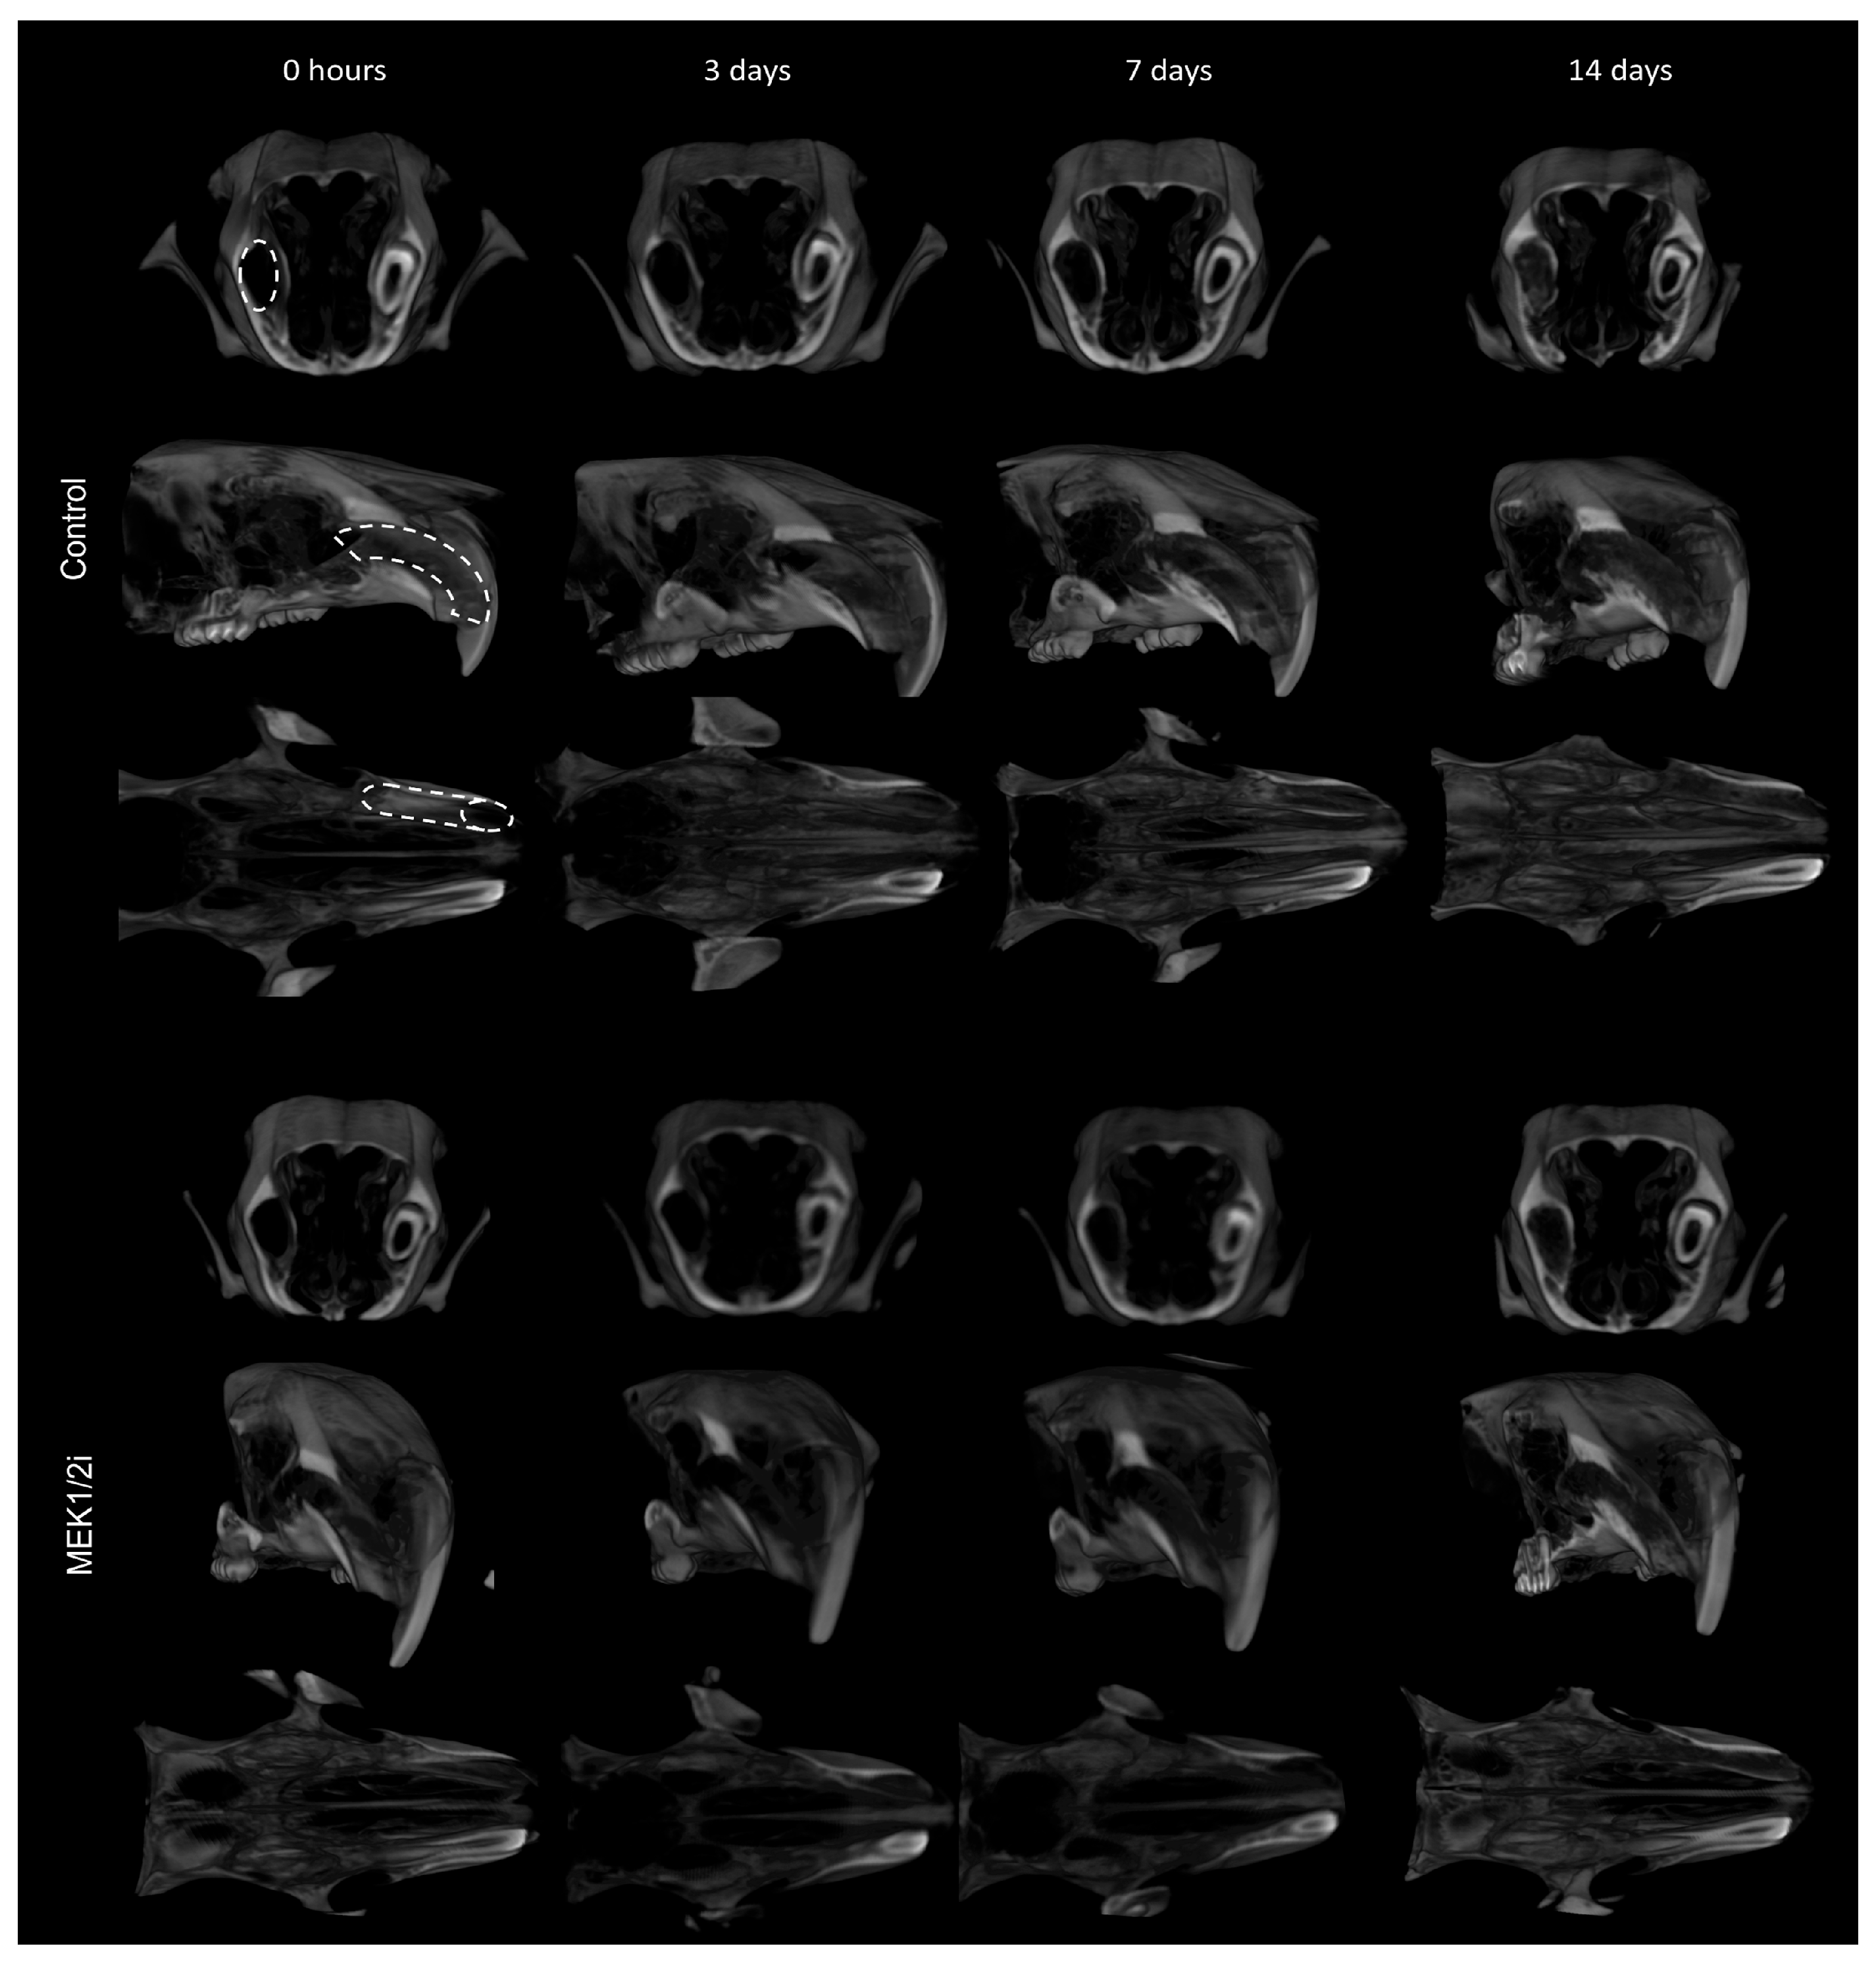

3.3. Bone Microarchitecture Between Groups Throughout the Evolution of Dental Socket Repair